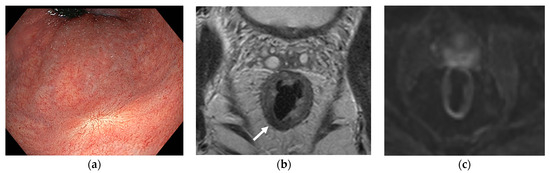

7.1. Non-Operative Management

7.2. Patient Selection